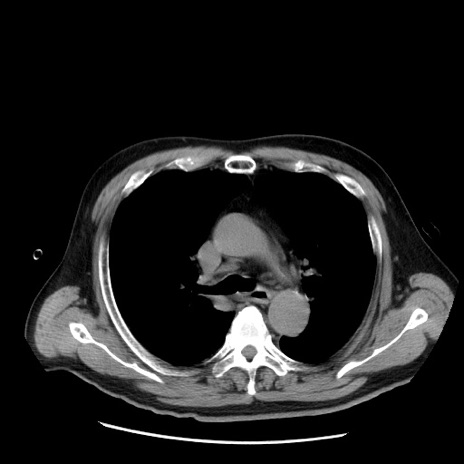

症例20(横断像)

【症例】 60歳代男性

【主訴】 腹部膨満、嘔吐

【現病歴】5日前頃より倦怠感を認め食事量減少し4日前の朝嘔吐、食事摂取困難となった。 3日前近医受診し点滴施行され整腸剤などを処方された。 当日他院を受診し、腹部膨満著明、炎症反応の上昇(CRP10.8、WBC11200)あり、紹介受診となる。

【身体所見】 意識JCS1 受け答えがはっきりしないBP 111/57mHg、 P 67bpm、、BT35.2°C、SpO2 97%(RA)、 腹部:膨隆、打診で鼓音あり、全体的に圧痛有り、腸蠕動音(-)、反跳痛ははっきりせず。

【データ】WBC 11400、CRP 14.20